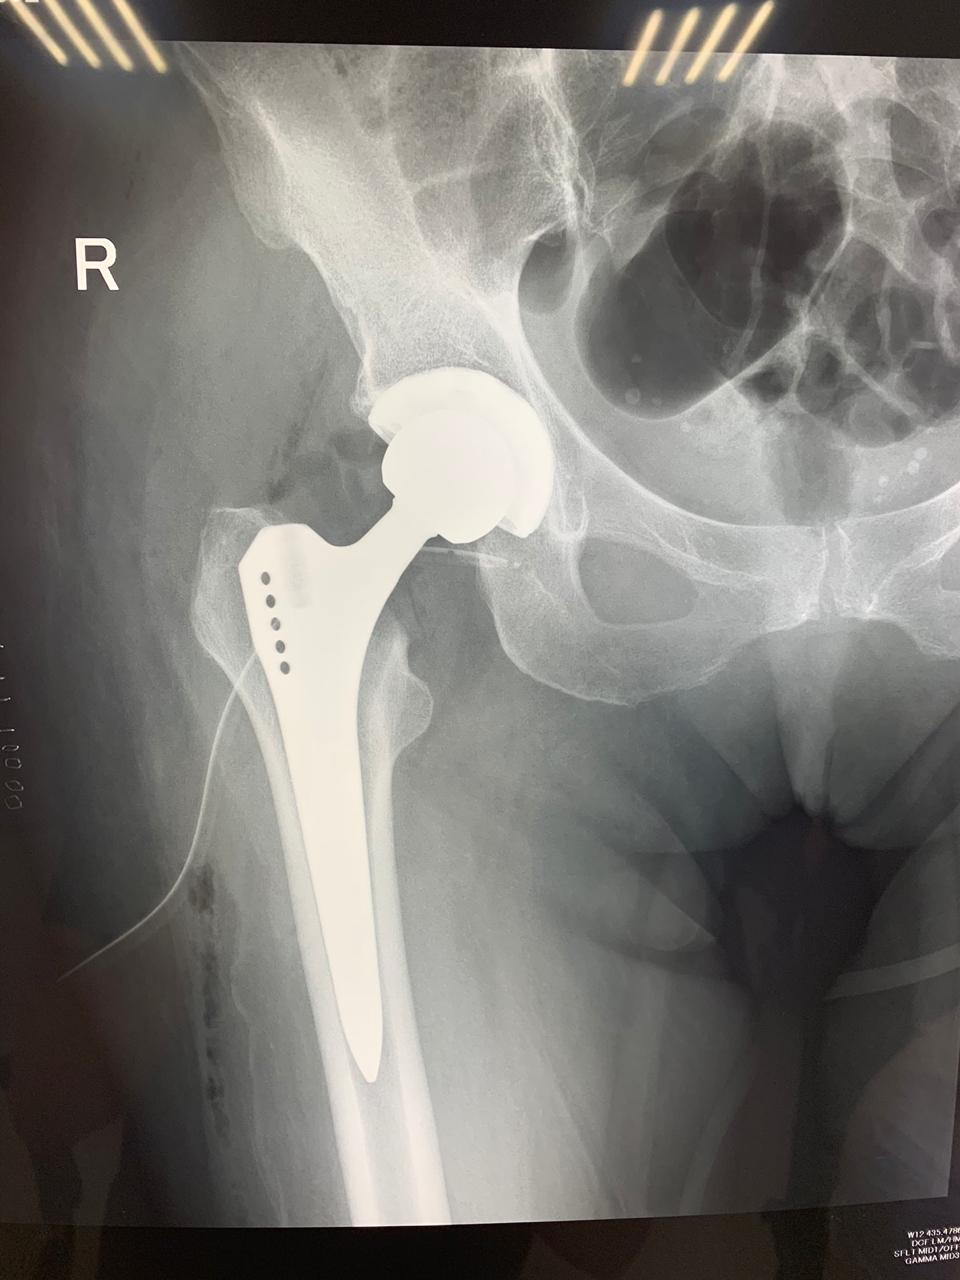

Эндопротезирование тазобедренного сустава: фото и схемы